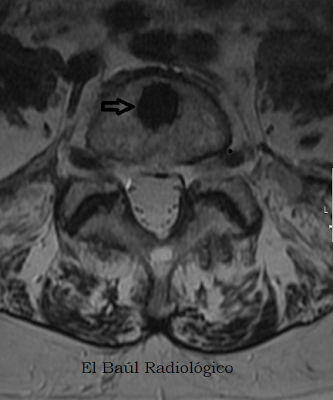

Enos+3.png

FIGURA 4) Vista de la lesión en proyección axial. Contorno nítido ligeramente espiculado. Diagnóstico: Enostosis.

(View of the lesion in axial projection. Well outlined: Diagnosis: Enostosis).